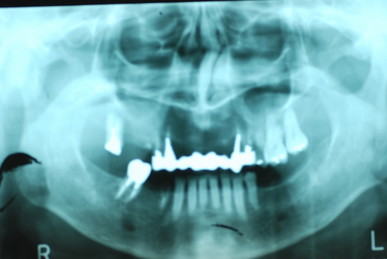

二ヶ月後ですが、歯周病が酷くなったので一時的に矯正治療を中止しました。歯周ポケットの深さを測っています。

挿入したゴムのポイントです。

歯並びは綺麗になり掃除はしやすくなったはずですが、矯正治療中は

磨きにくいので歯周病や虫歯が酷くなりやすいのです。